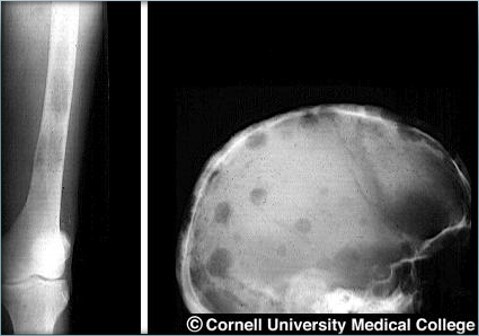

multiple myeloma

lytic lesions

• Bony destruction caused by accumulation of plasma cells

• Plasma cells increase bone absorption resulting in bony destruction

“Punch out” lesion

Hypercalcemia

Pathologic fractures

Lytic Lesions: most common Sx

Pain back, hips, and skull

Bone weakness – osteoporosis or plasmacytoma

Fractures